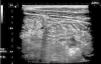

Presentamos el caso de un niño de 10 años, diagnosticado de HAE por déficit cuantitativo de C1 inhibidor, que acude a urgencias de nuestro hospital por un cuadro dolor abdominal difuso, de tipo cólico, de 8 h de evolución, acompañado de vómitos y anorexia. En la exploración física el paciente se encontraba afebril, con regular estado general, destacando un abdomen duro y muy doloroso a la palpación. Los parámetros de hemograma, proteína C reactiva, perfil hepático y renal se encontraban dentro de la normalidad. La ecografía de abdomen mostró un engrosamiento difuso de la pared del intestino delgado, que consistía en colecciones de líquido en la mucosa, incremento del líquido intraluminal y moderada ascitis. El intestino grueso y el apéndice no presentaban alteraciones (fig. 1). Se administraron 500 U de concentrado de C1 inhibidor por vía intravenosa. A las 2 h del tratamiento, los síntomas desaparecieron y se repitió la ecografía de abdomen, que mostró la desaparición de las colecciones quísticas en la mucosa y disminución del líquido intraluminal (fig. 2).

La realización de ecografía abdominal durante los episodios de ataque agudo de HAE permite detectar signos que, aunque no son específicos, son muy sensibles, como el edema de la pared intestinal, hiper o hipomotilidad intestinal y líquido libre en la cavidad peritoneal. Además, la presencia de colecciones líquidas entre las capas de la mucosa y submucosa apoyan fuertemente el diagnóstico. Según la literatura, el edema de la pared intestinal se detecta con menos frecuencia que la ascitis. El seguimiento ecográfico de estos pacientes tras el tratamiento demuestra la reabsorción de la ascitis, acompañada de la desaparición del edema de la pared intestinal5-10. Existen diversos estudios comparativos entre la tomografía computarizada y la ecografía en el diagnóstico de afectación abdominal por HAE, encontrando buena correlación entre ambas técnicas. Aunque la ecografía es menos sensible para detectar edema de la pared intestinal, es más coste-eficiente y está exenta de radiación ionizante6. Encontramos que la ecografía podría ser una técnica apropiada para el diagnóstico diferencial de dolor abdominal agudo en pacientes con HAE. De esta manera, se evitan pruebas más agresivas e intervenciones quirúrgicas innecesarias, además de ayudar a un diagnóstico y tratamiento precoz en aquellos pacientes aún no diagnosticados de la enfermedad.